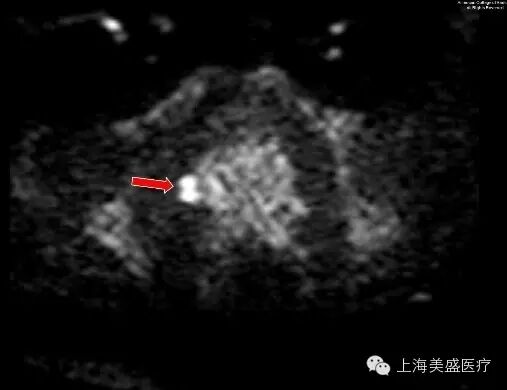

图 2. 前列腺周围带右侧区 T2 低信号区在 DWI 表现为高信号(箭头示)